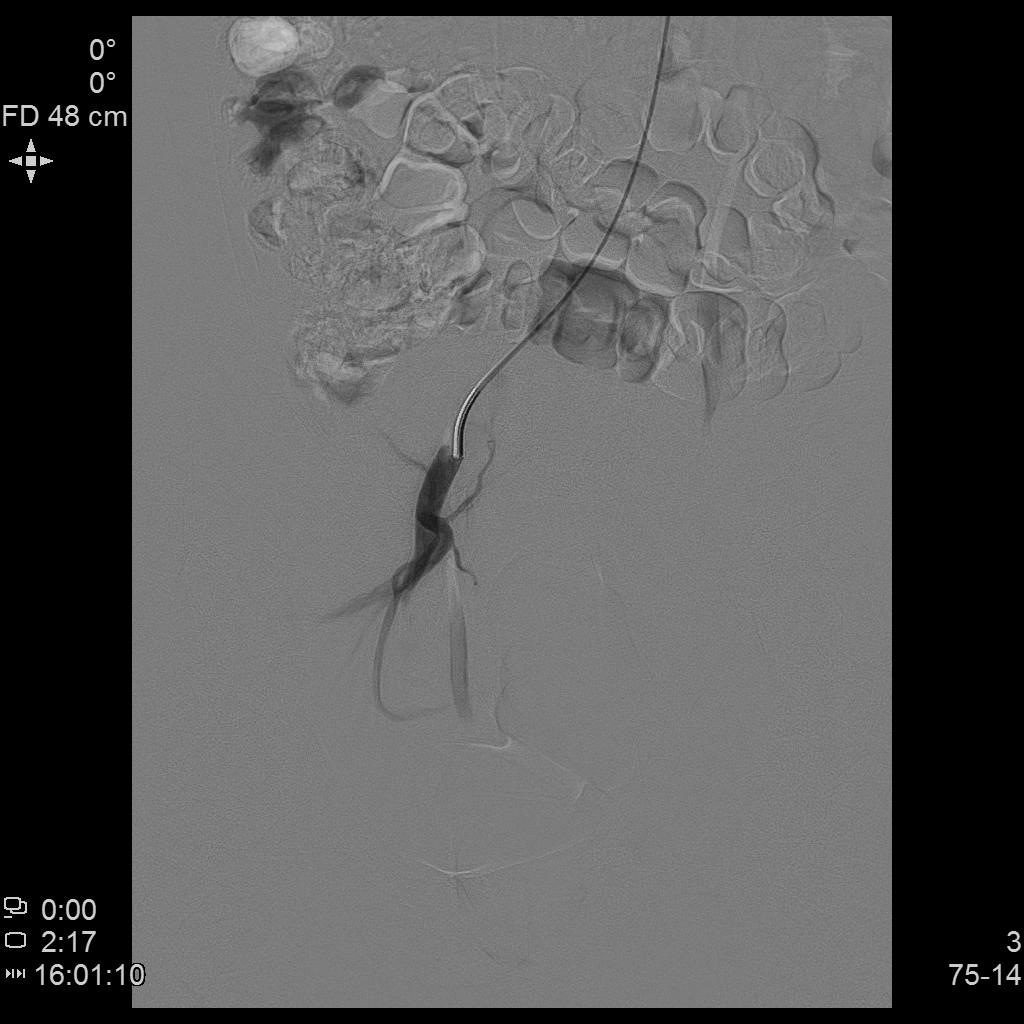

- 进一步超选插管左侧子宫动脉造影确认位置

- 微导管进一步超选插管左侧子宫动脉主干造影确认位置

- 栓塞术后复查造影显示左侧子宫动脉分支末梢未见显示